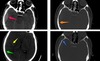

45

Label the types of extra-axial bleed occuring at the red; yellow & green arrows [3]

**red arrow: EDH** brown arrow shows how EDH respects the suture margins **yellow arrow points at SAH** **green arrow: SDH** blue arrow shows the fracture

46